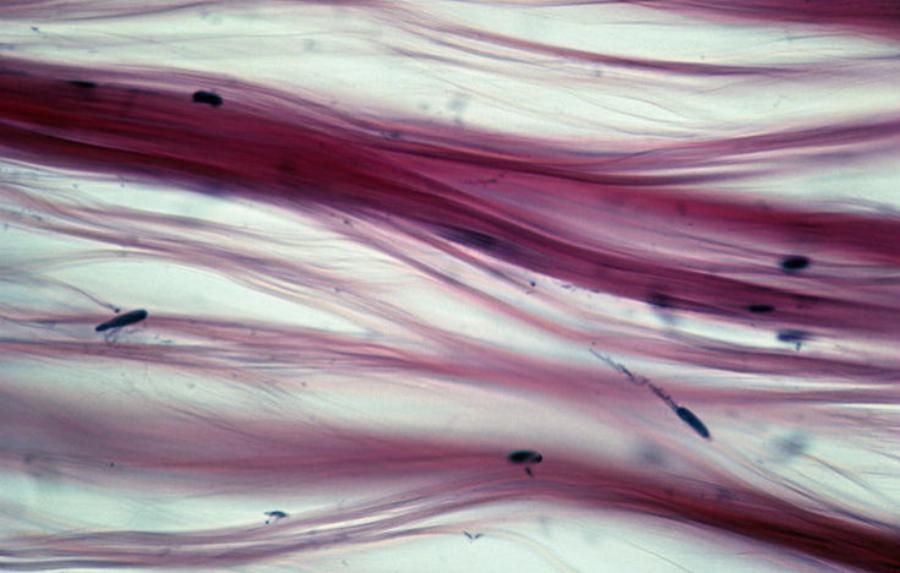

Το Σκληρόδερμα ή Συστηματική Σκλήρυνση είναι ένα χρόνιο, αυτοάνοσο νόσημα του συνδετικού ιστού.

Τα συμπτώματά του, τα οποία διαφέρουν από άτομο σε άτομο, μπορεί να είναι ορατά, όπως οι εμφανείς αλλοιώσεις του δέρματος ή μη ορατά, όπως η προσβολή των εσωτερικών οργάνων. Για την εκδήλωσή του ενοχοποιούνται κυρίως γονιδιακοί παράγοντες, περιβαλλοντικοί, μικροβιακοί και ιογενείς.

Το Σκληρόδερμα εκδηλώνεται με πάχυνση του δέρματος και στη συνέχεια γίνεται πιο σκληρό, χάνει την ελαστικότητα του μεταβάλλεται το χρώμα του και δίνει την εικόνα της δερματίνης. Σκλήρυνση του ιστού μπορεί επίσης να εκδηλωθεί στα νεφρά, τους πνεύμονες, την καρδιά και την γαστρεντερική οδό. Η φαρμακευτική αγωγή μπορεί να ανακουφίσει τα συμπτώματα. Η άσκηση μπορεί να βοηθήσει στη διαχείριση του πόνου και τη βελτίωση της αντοχής και της κινητικότητας.